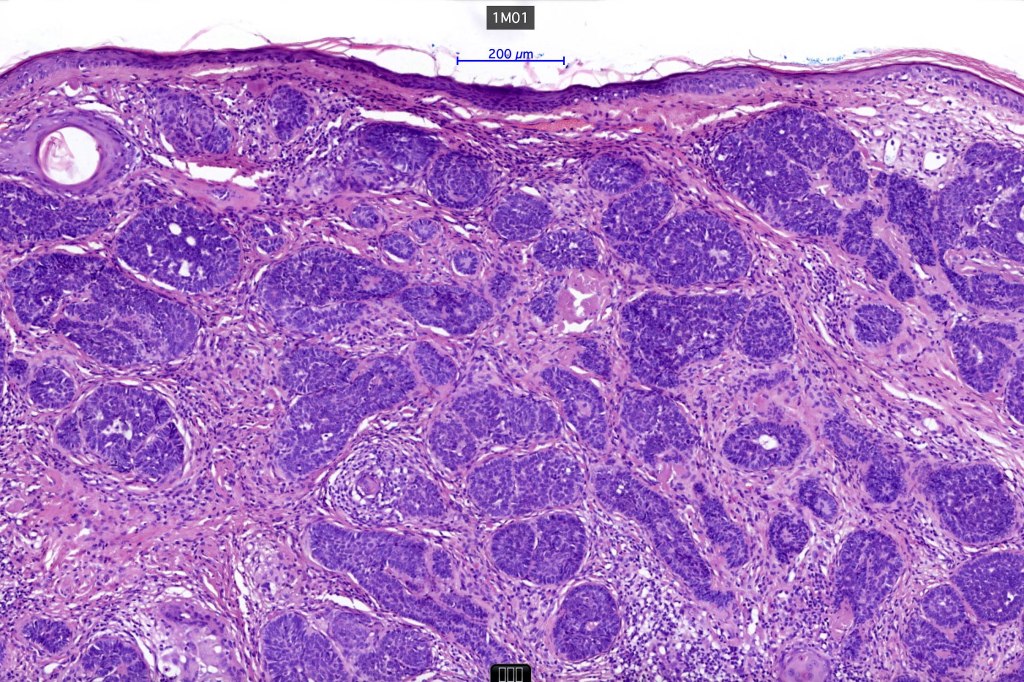

Histological features

•The classical appearance consists of keratocysts & lobules of basaloid cells

•Some tumors are devoid of keratocysts

•Variable continuity with the epidermis

•Basaloid lobules show peripheral palisading

•Retraction artifact and mucin deposition as seen in BCC are not present

•Mitoses & apoptosis may be present

•Perifollicular mesenchyme is always conspicuous and sometimes densely aggregated are seen indenting the baslaloid lobules (papillary mesenchymal bodies)

•Narrow epithelial strands arising from the basaloid lobules are often present

•Amyloid, foreign body granuloma formation to free keratin & calcification are variable features

Trichoepithelioma should be distinguished from trichoblastoma since the latter is very rarely syndromic. Trichoepithelioma is largely a dermal tumor whereas trichoblastoma often extends from the dermis into subcutaneous fat or deeper in very large examples. Papillary mesenchymal bodies are much better formed and generally more obvious in trichoepithelioma. Trichoepithelioma must also be distinguished from basal cell carcinoma. Retraction artifact & stromal mucin are features of basal cell carcinoma and not trichoepithelioma. Papillary mesenchymal bodies are not seen in basal cell carcinoma.